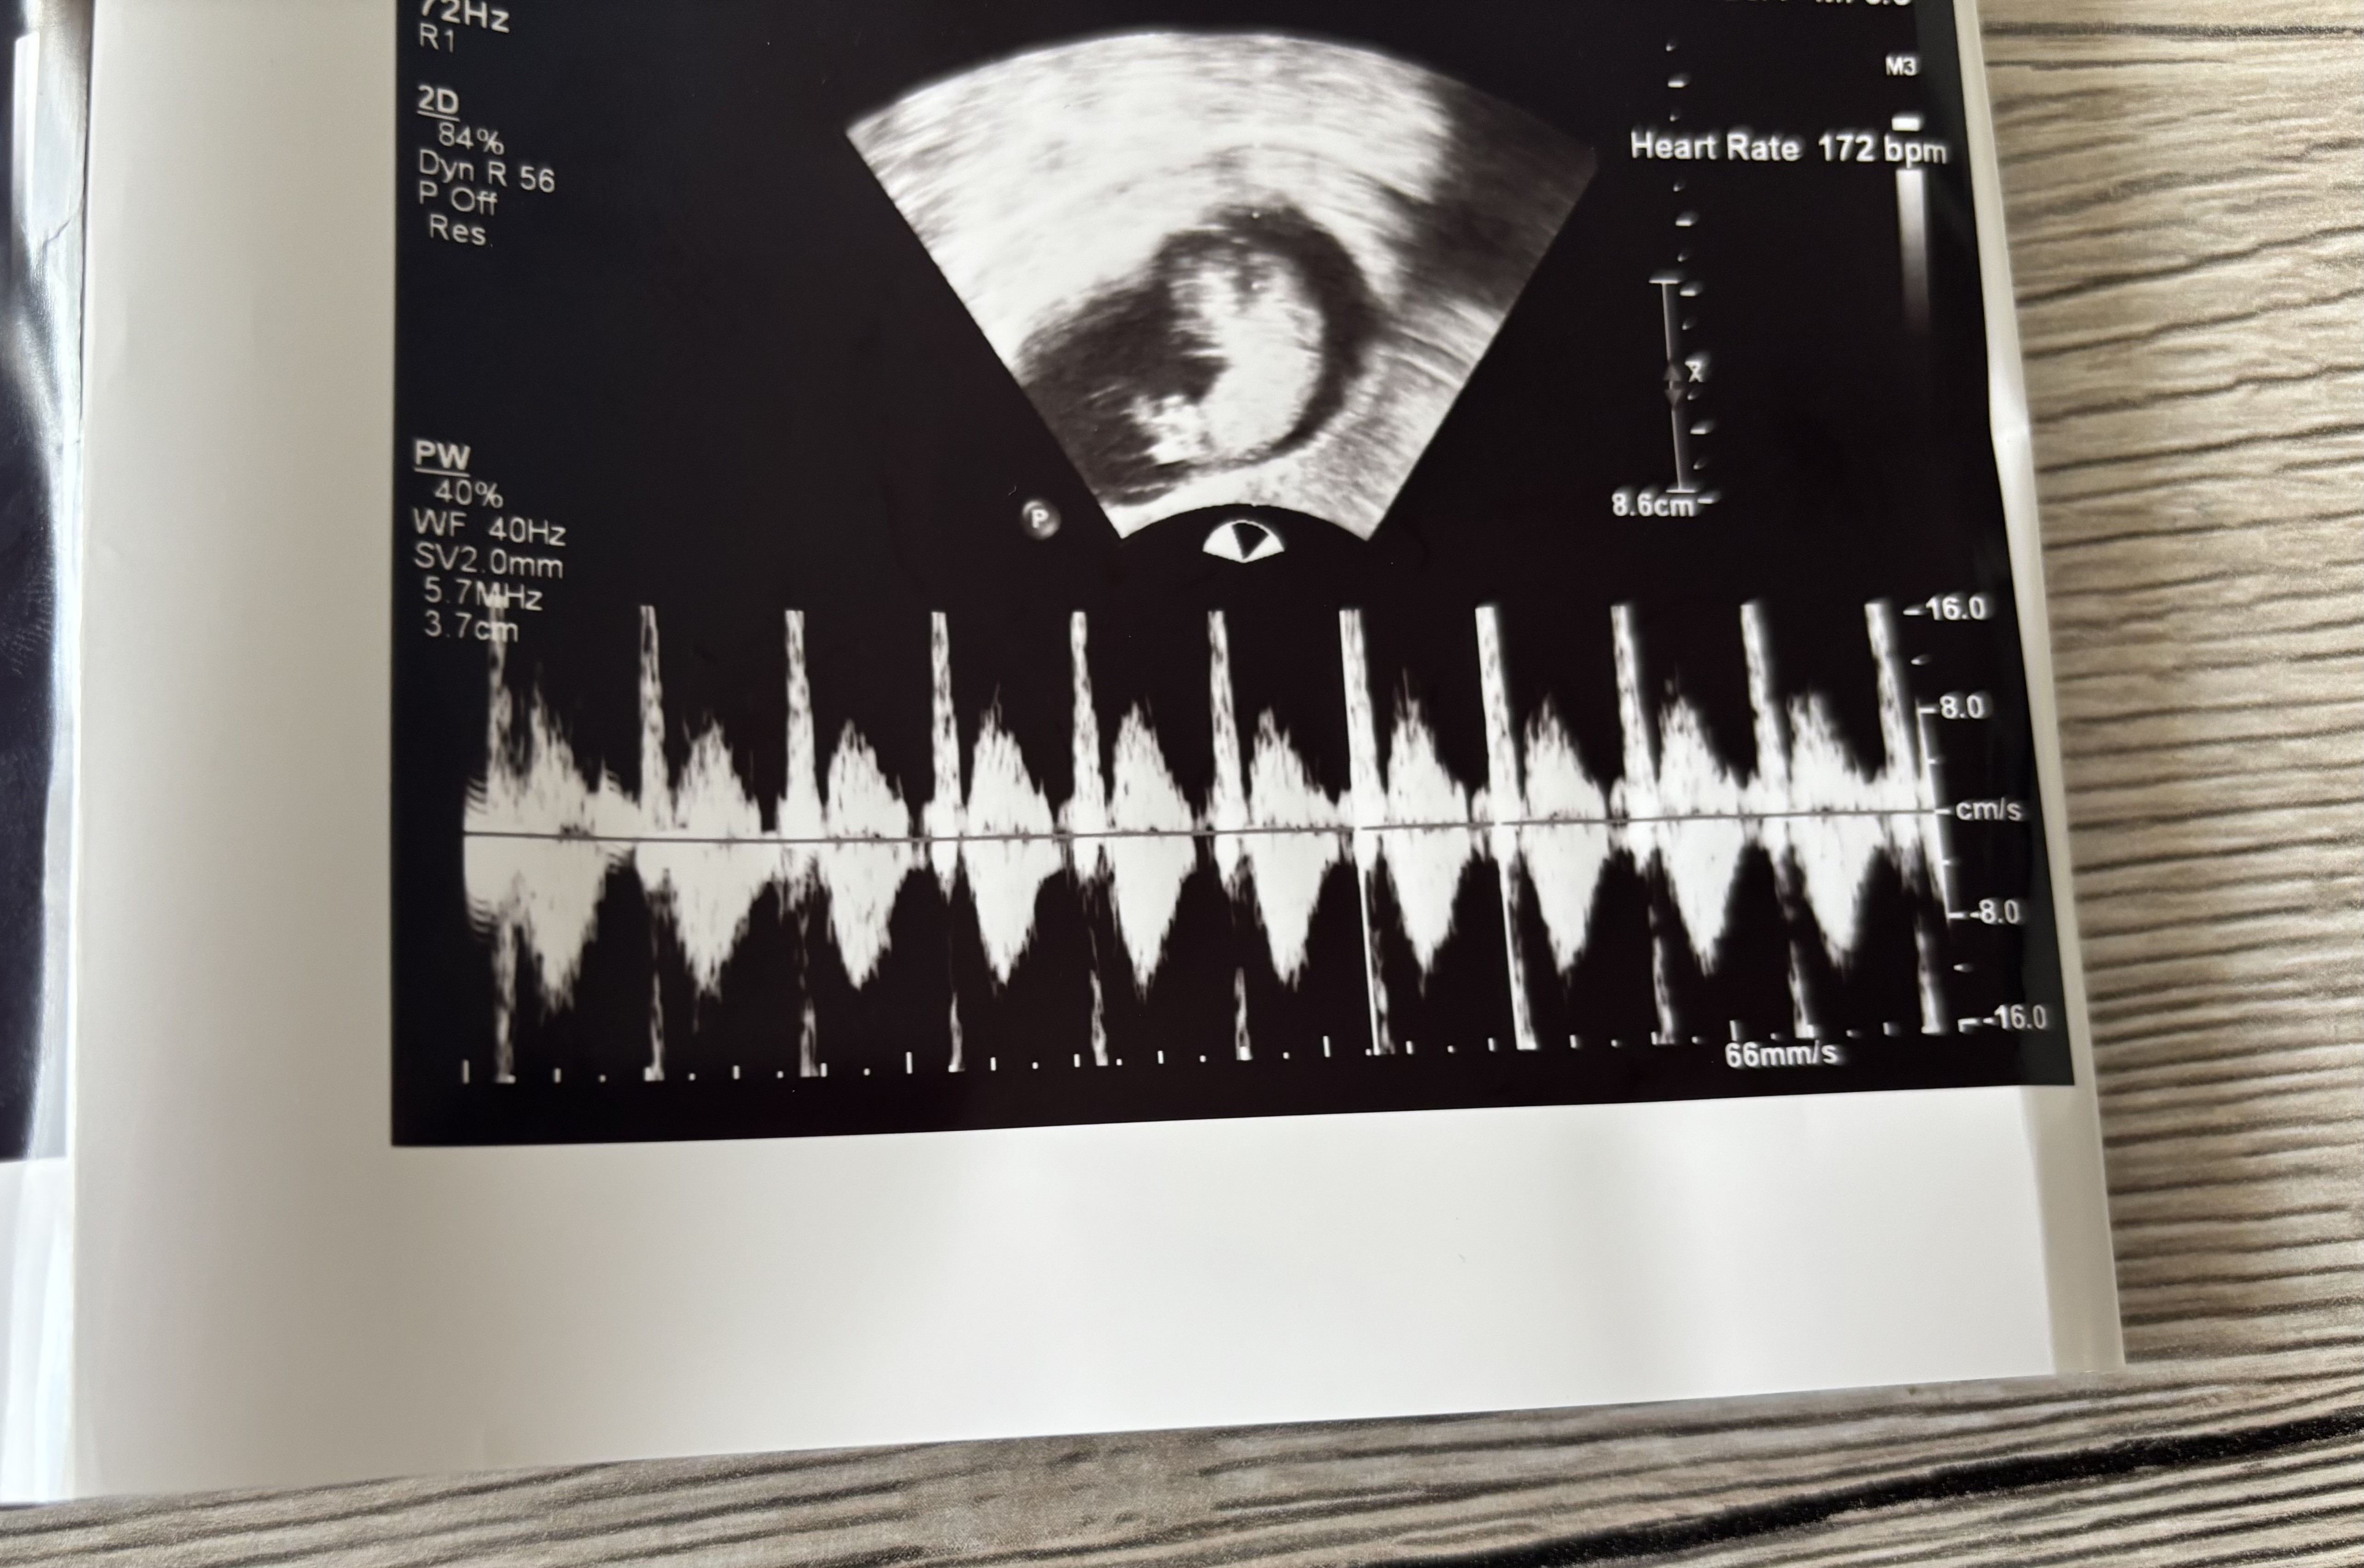

Dziewczyny jestem taka szczęśliwa moje maleństwo ma 3,2cm i jest o jeden dzien większe. Słuchalismyserduszka bije 172 bpm. Termin mi się zmienił ale na razie zostawiam taki jaki był. Ma 2 raczki i 2 nóżki a w brzuchu był taniec 💃🏼 🕺🏼

• IMG_3169.jpeg

IMG_3169.jpeg

2,1 MB · Wyświetleń: 95